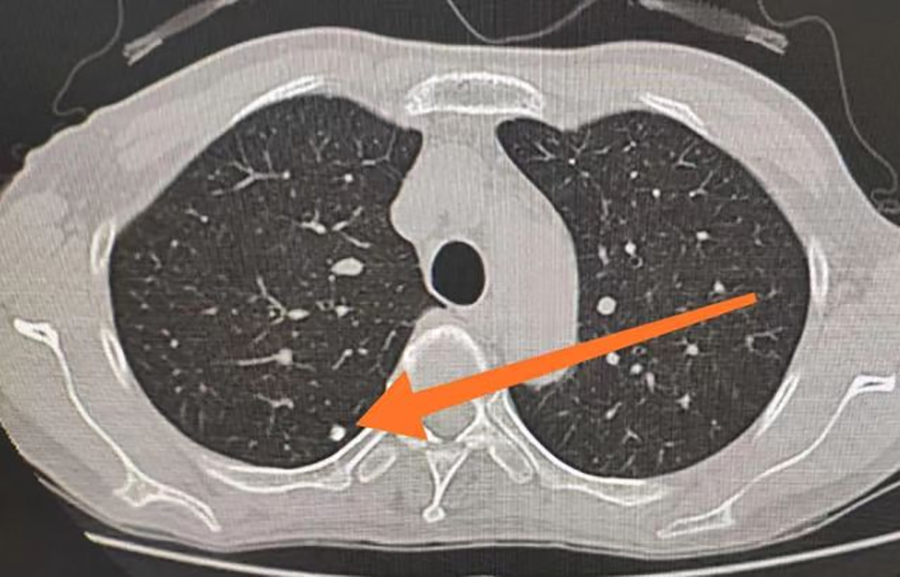

肺结节意味着得了肺癌吗?要做手术吗?同样的问题也困扰着40岁出头的李先生。一次体检中,李先生被查出双肺肺实性结节,最大的约6mm,这着实把他吓了一跳。因为不了解肺结节,让他产生了紧张、恐慌、焦虑情绪。于是,他便来到了红桃视频 平阳部肺病科就医。平阳部肺病科副主任王丽娜说,肺结节是影像学表现为直径≤3cm大小,局灶性、类圆形、密度高的阴影,通常不会引起临床症状,起病隐匿、不易发现,是近年来的常见病。其中,直径≤1cm时通常被描述为小结节,而直径≤0.5cm时被称为微小结节。除了大小以外,还根据结节的密度不同分为纯磨玻璃结节、部分实性磨玻璃结节和纯实性结节。

王丽娜说,临床上初次发现的肺部结节多数为良性病变。良性结节大多数是肺结核或者肺部炎症,经过治疗之后,局部组织形成瘢痕性的修复,从而表现为结节。但是,其中仍有一定比例为恶性肿瘤早期表现,比如伴有分叶、毛刺、胸膜凹陷征、支气管截断征、支气管充气征、血管集束征等变现,则考虑恶性病变的可能性较大。所以,在确诊为肺部结节后,大家也无需过度恐慌,一定要遵医嘱定期复查肺CT,以明确结节有无增长以及形态变化等问题。